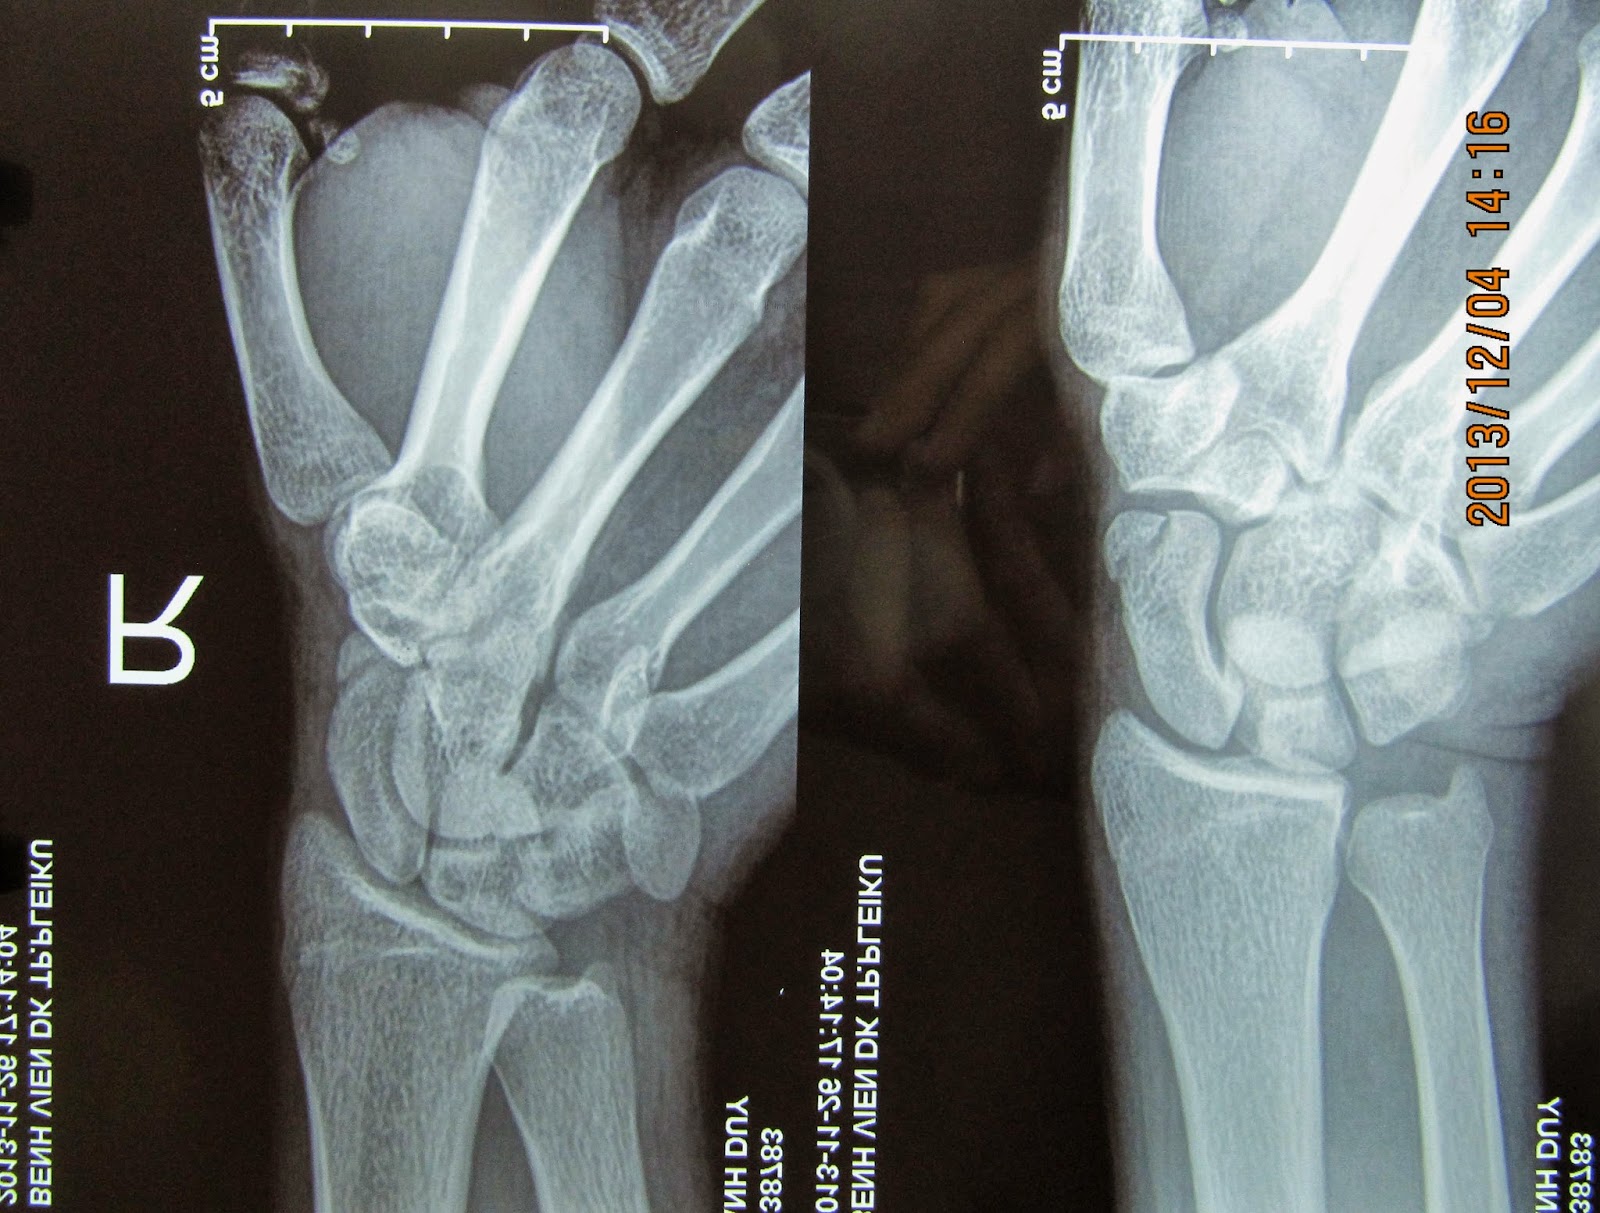

Gãy xương thuyền

• Chụp X-quang sẽ giúp xác định chẩn đoán.

Gãy xương thuyền - Hình ảnh minh họa

Click vào ảnh để xem 4 hình ảnh minh họa